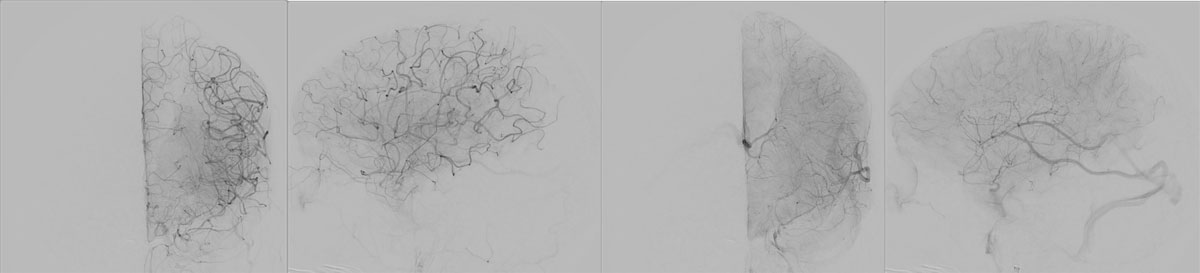

EVT Strategy

• Inflate the balloon, in order to dilate the true lumen

• MCA access with the softest system possible

• Open a stentriever for 20 mins with antiplatelet infusion

• Resheath the stentriever, check patency, if not stent-deployment

Headway™ DUO 156cm / Traxcess™ 14

CatchViewMini20

pEGASUS 4x20mm